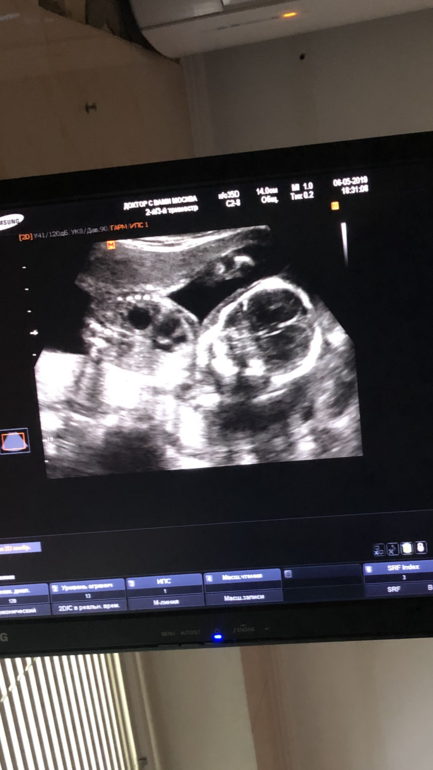

Мальчик или девочка?)

Знаю, что тут девочки глазастые, а я даже не понимаю, что где на фото, кроме головы))

Видно там половые принадлежности или он боком?) 20 недель

На второй Фотке, я так понимаю, должно быть видно. Но, честно, я не понимаю в этих куконях ничего😂

Вроде лежит на боку и лицом к аудитории ) и я вижу, что это девочушка ))

Попку видно). А вам не сказали ,срок большой уже?